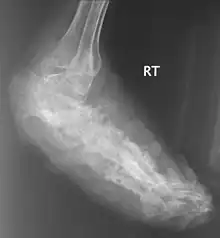

X rays and ultrasonography may be carried out to assess the extent of the disease. X rays findings are extremely variable. The disease is most often observed at an advanced stage that exhibits extensive destruction of all bones of the foot. Rarely, a single lesion may be seen in the tibia where the picture is identical with chronic osteomyelitis. Cytology of fine needle aspirate or pus from the lesion, and tissue biopsy may be undertaken sometimes.[11] Some publications have claimed a "dot in a circle sign" as a characteristic MRI feature for this condition (this feature has also been described on ultrasound).[14]